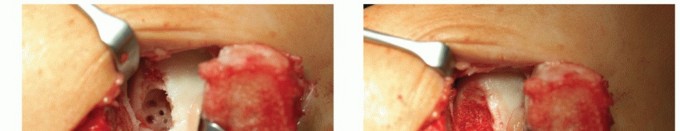

Using a curette, harvest two or three full-thickness articular grafts that include the superficial layer of subchondral bone (TECH FIG 1). The grafts are transferred to a sterile container and transported to the laboratory. Using a patented procedure, the articular cartilage matrix is enzymatically disrupted to isolate the chondrocytes. Culturing of chondrocytes requires about 2 to 6 weeks, depending on the company and the preferred culturing process.

- TECH FIG 1 • A. Harvesting cartilage with a curette from the ventral aspect of the talus. B. Grasping the small piece of cartilage for culturing.

- TECH FIG 2 • A. Traumatic osteochondral lesion at the medial talar dome after removing the unstable cartilage and the subchondral cyst. The sclerotic wall of the cyst shows several drillholes. B. Defect filled with autologous bone graft. C. Container with the matrix induced condrocytes, ready for transplantation. D. Matrix-induced chondrocytes transplanted into the defect and fixed with fibrin glue.

Take care when removing the transplant from the transport container. In particular, avoid squeezing the transplant (TECH FIG 2A,B).

Cut the transplant according to the size of the defect. Some companies provide special punches for this step. The size of the transplant should meet exactly the size of the defect. Preparing the transplant 2 mm larger, as recommended for the periosteal flap, can lead to overlaying edges and a lack of stability.

Place the transplant into the defect. A first fixation happens due to adhesion forces. The edge can then be stabilized with 6-0 sutures and fibrin glue (TECH FIG 2C,D).